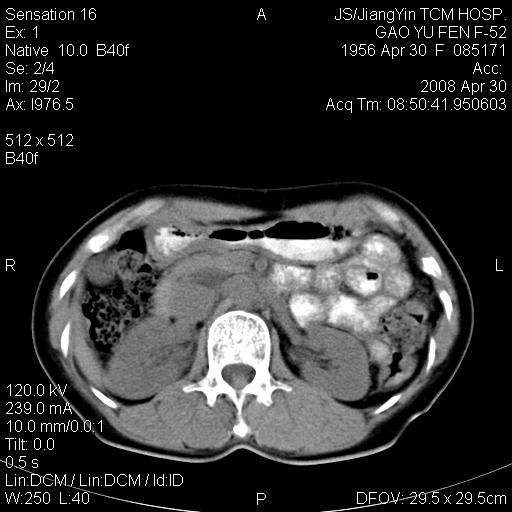

标题: CT13307:肠系膜囊肿? [打印本页]

标题: CT13307:肠系膜囊肿?

积液?囊肿?脂肪瘤?

良性囊性占位,来源于肠系膜的可能性大

图像少,不能连续起来看,不太敢确定囊肿前方的条状结构是十二指肠水平段?如果是,那肠系膜囊肿,淋巴管瘤都有可能。

病变位于肾静脉后方,支持腹膜后占位性病变,以囊性淋巴管瘤可能性大.